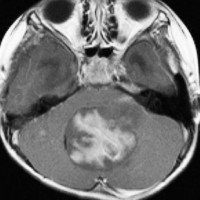

多房性白質壊死 multicystic white matter malacia

放射線により脳の髄鞘を形成する乏突起膠細胞 オリゴデンドロサイトoligodendrocyte (乏突起膠細胞)が障害を受け,脱髄 demyelinaiton が生じて白質脳症となります。上記の例はその病理像を反映するMRI所見です。

脳微小血管内皮細胞の放射線障害によって白質が小さな虚血性梗塞となり,白質壊死 white matter necrosisという重い白質脳症もあります。この場合は画像で脳の内部に穴の開いたような像(軟化巣)がみられます。上の画像は,35グレイの全脳照射を受けた5歳の子どものものです。左側が鞍上部ジャーミノーマの治療前のもの,右側は放射線治療2年後のものです。脳の中にたくさんの穴が開いています。これをのう胞性軟化巣 cystic malacia といいます。白質脳症の最も重いかたちのものです。